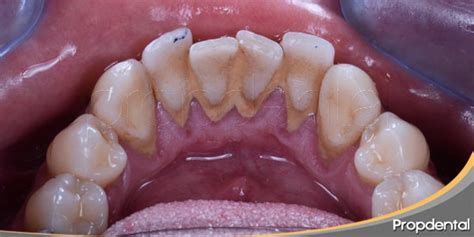

El sarro, también conocido como cálculo dental o tártaro, puede producir uno de los problemas bucodentales más frecuentes, a pesar de que muchas personas no le dan demasiada importancia. El sarro en los dientes es una acumulación endurecida de placa bacteriana, formada por la mineralización de restos de alimentos, bacterias y saliva. Este depósito calcificado suele ser de color amarillo o marrón y se adhiere firmemente a la superficie de los dientes, siendo difícil de eliminar con la simple acción de cepillado.

El sarro, a veces denominado cálculo o tártaro dental, es la placa que se ha endurecido en los dientes debido al depósito de minerales. El sarro, conocido científicamente como cálculo dental, es una acumulación endurecida de placa bacteriana en los dientes. La placa es una mezcla pegajosa de bacterias, saliva y restos de alimentos que, si no se elimina adecuadamente, se mineraliza convirtiéndose en sarro. Este proceso se ve acelerado por sustancias en la saliva que facilitan la cristalización de los minerales.